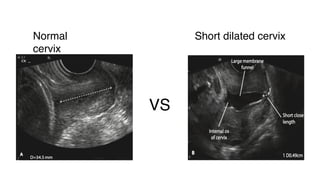

Cervical insufficiency

Painless dilatation of cervix in the 2ndor early in the 3rd trimester

Diagnosis

History 2ndor early in the 3rd trimester loss

Ultrasound +- TVS

VS

Normal

cervix

Short dilated cervix